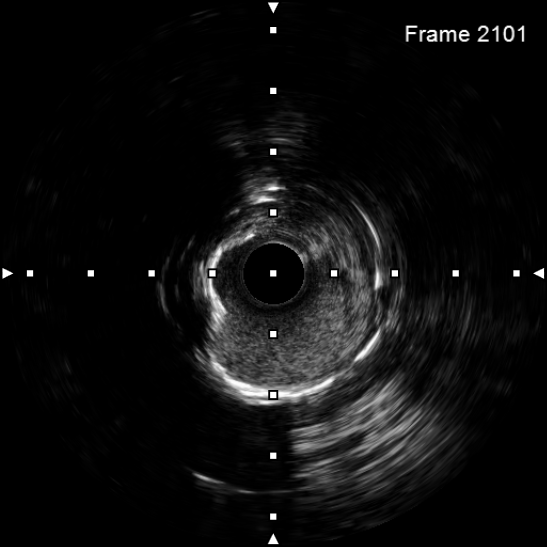

图4 3.0 Shockwave处理后可见钙化断裂 高压球囊验证膨胀良好

该患者入院后,完善相关检查并再次建议行CABG治疗,但家属仍拒绝,遂考虑再次行PCI手术干预。冠脉造影提示患者冠脉右冠状动脉中段70-95%再狭窄,左主干末端80%狭窄,前降支原支架中远段 80-95%再狭窄,回旋支完全闭塞,急需手术尽快解决冠脉血流灌注问题,否则随时有生命风险,但患者多处支架内/节段内再狭窄,造影提示钙化明显,外院已尝试无法扩张,经手术团队充分讨论后,计划在IABP支持下,先进行右冠状动脉干预,利用IVUS精准评估原支架再狭窄部位情况,采用旋磨或Shockwave冲击波球囊处理无法扩张的病变部位,右冠处理后择期进行左冠状动脉干预。在制定了详尽的手术计划后,手术团队首先对患者的右冠状动脉行IVUS检查,结果提示该患者右冠中段支架局部膨胀不良,局部支架面积6.67mm²,管腔内多处可见钙化小结及270°以上钙化,IVUS钙化积分达3分。由于膨胀不良处原支架后方可见钙化斑块,常规旋磨效果不佳,对于此类钙化病变,IVL处理是最佳方案。手术团队对近端采取棘突球囊及高压球囊进行扩张,采用Guidezilla辅助下输送3.0mmx12mm Shockwave冲击波球囊于右冠钙化处进行冲击波钙化斑块碎裂术,通过IVUS证实支架内的新生钙化病变得到松解,原膨胀不良部位支架面积达到7.76mm²,后经过高压球囊充分预处理,顺利完成右冠支架植入,术后复查右冠原膨胀不良部位支架面积9.17mm²。

2天后再次干预患者左冠状动脉,首先开通回旋支并进行球囊扩张,采用IVUS进行前降支至左主干支架评估,IVUS提示左主干末端原支架内可见新生环状钙化病变,采用3.0x12mm Shockwave预处理后可见钙化断裂,并再次经高压球囊预处理,于前降支至左主干植入支架,术后造影及IVUS均提示支架膨胀良好,左主干MSA 9.96mm²。患者经介入干预后,胸痛症状较前明显缓解,体力活动较前恢复。